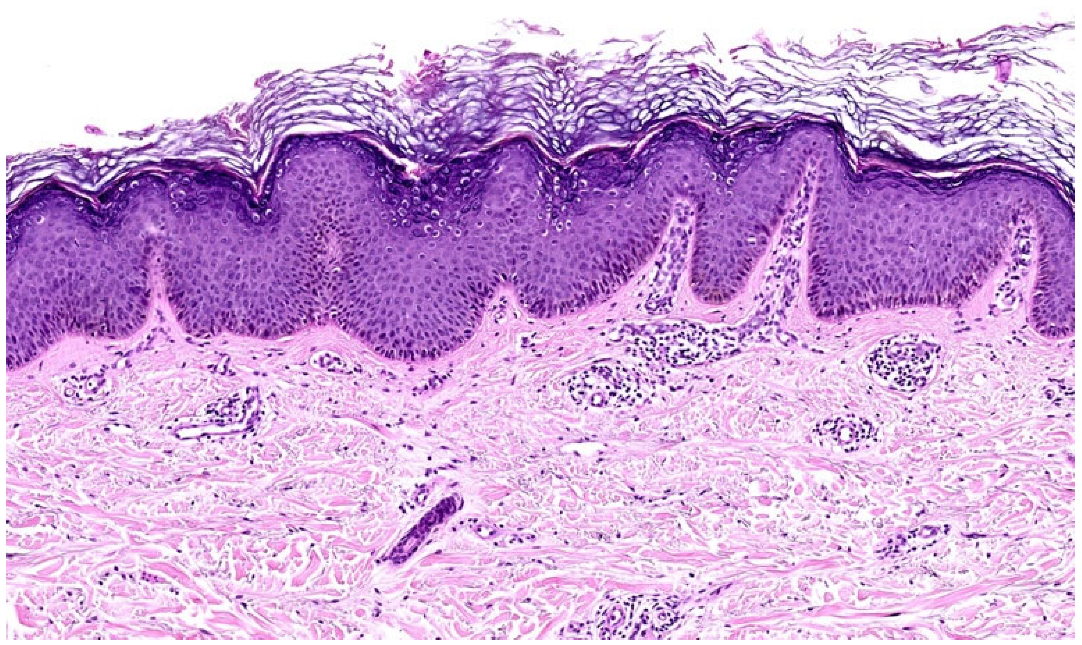

3.2.3. Lichen Simplex Chronicus (LSC)

| LSC | Scaling lichenified with overlying excoriation, areas of hyper/hypopigmentation | Not wedge-shaped | Severe | Regular/irregular | Present | Increased fibrocyte number; thickened papillary dermis | Good response to therapy |